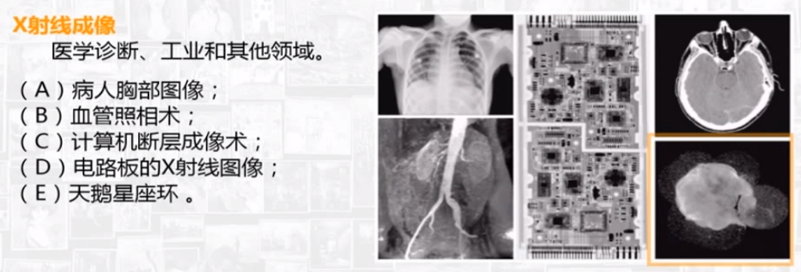

电磁波图,波长从小到大,包括伽马射线、x射线、紫外线、可见光、红外线、无线电波